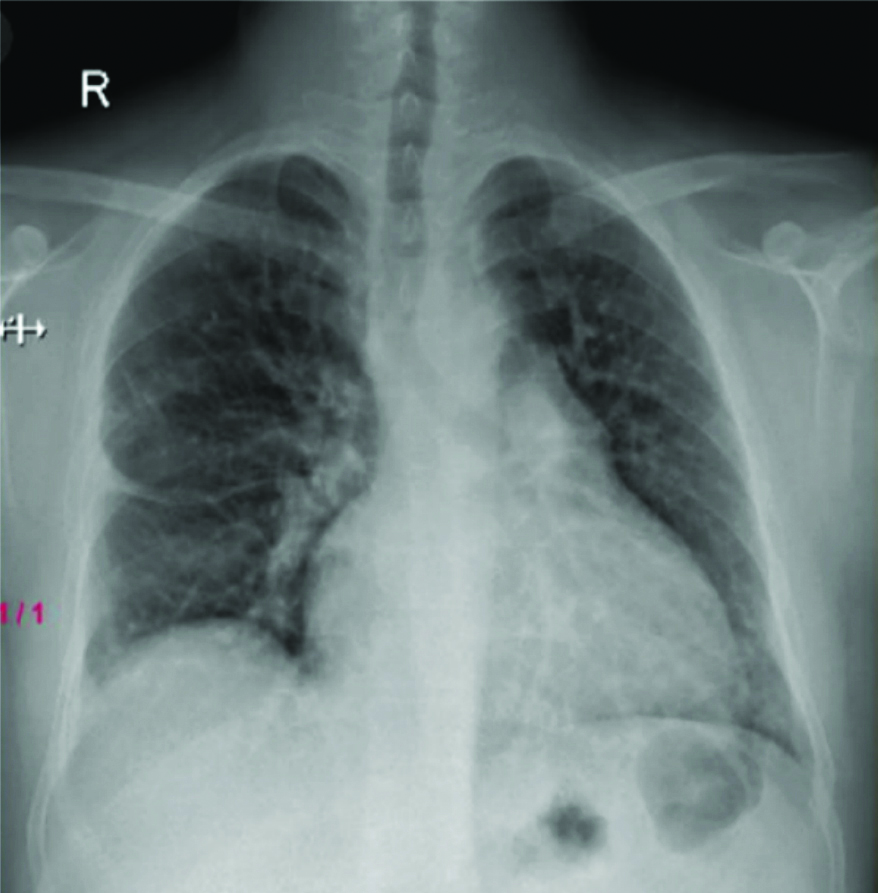

Radiological investigations included a chest X-ray showing right middle and lower zone homogeneous opacity obliterating the right cardiophrenic and costophrenic angles, suggestive of right pleural effusion [Table/Fig-2]. An ultrasound of the thorax indicated a gross right pleural effusion (>1000 cc) with internal septations. High-Resolution Computed Tomography (HRCT) and CT Pulmonary Angiogram (CTPA) confirmed the gross right pleural effusion without evidence of thromboembolism [Table/Fig-3]. It showed a large abnormal communication between the left distal ascending aorta and the right wall of the main pulmonary artery [Table/Fig-4].

Chest X-ray showing right middle and lower zone homogenous opacity (red arrow) with obliteration of the right cardiophrenic and costophrenic angles.